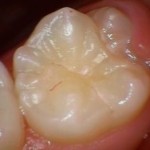

シーラント処置前

-

シーラント処置後

虫歯のなりかけであれば再石灰化と言われる歯の再生も見込めるので、むやみに歯を削らず、定期検診で歯の状態をチェックしていきます。